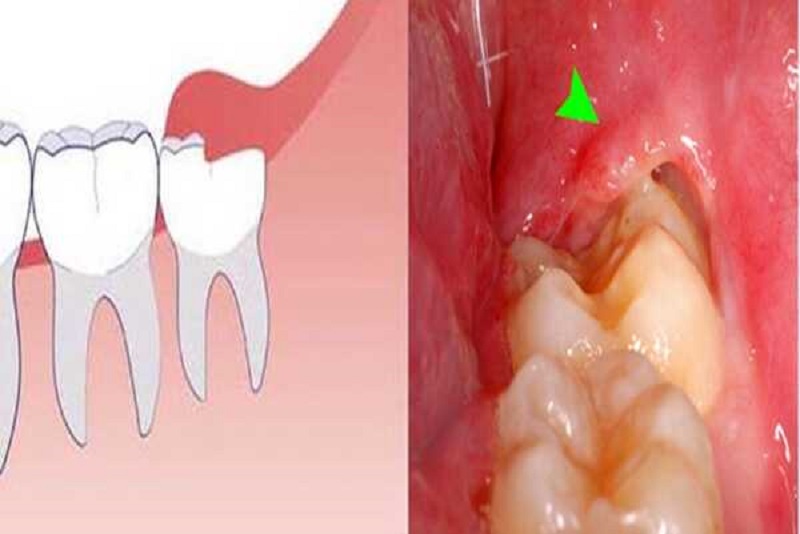

- Răng số 8 bị sâu: vì không đủ khoảng trống để mọc nên răng khôn thường mọc rất gần, thậm chí chen lấn vào các răng kế bên. Không gian chật hẹp này khiến việc vệ sinh, làm sạch gặp rất nhiều khó khăn, tạo điều kiện thuận lợi để mảng bám hình thành và gây ra sâu răng. Sâu răng phát triển sẽ gây ra những cơn đau nhức nghiêm trọng, thậm chí có thể ảnh hưởng cả đến các răng lân cận.

Hình ảnh răng số 8 bị sâu vỡ